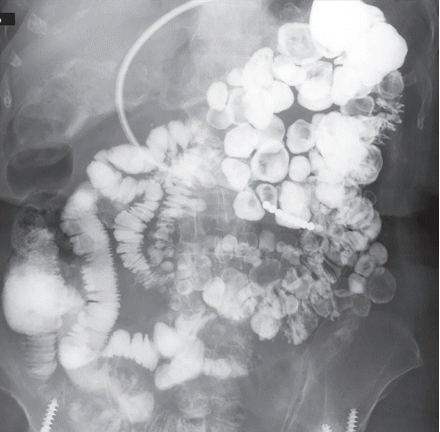

An 82-year-old female presented with melena. She had been on thrice-weekly conventional hemodialysis for 8 years. An esophagogastroduodenosopy and colonoscopy revealed no bleeding source. A small bowel series revealed multiple round-shaped jejunal diverticula (Fig. 1) and balloon enteroscopy confirmed large diverticula in the jejunum (Fig. 2). Diverticular bleeding was clinically suspected despite the absence of bleeding stigmata and she improved conservatively.

Figure 1.

A small bowel series showing jejunal diverticulosis.